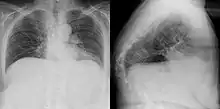

Gibbus deformity is a form of structural kyphosis typically found in the upper lumbar and lower thoracic vertebrae, where one or more adjacent vertebrae become wedged. Gibbus deformity most often develops in young children as a result of spinal tuberculosis and is the result of collapse of vertebral bodies.[1][2][3] This can in turn lead to spinal cord compression causing paraplegia.[4][5]

Gibbus deformity is included in a subset of structural kyphosis that is distinguished by a higher-degree angle in the spinal curve that is specific to these forms of kyphosis. Other conditions within this subset include Pott's disease and Scheuermann kyphosis, but gibbus deformity is marked by an especially sharp angle. Viewed from behind, the resulting hunchback is more easily seen when bending forward.[10] A kyphosis of >70° can be an indication of the need for surgery and these surgeries can be necessary for children as young as two years old, with a reported average of 8 years of age.[9]